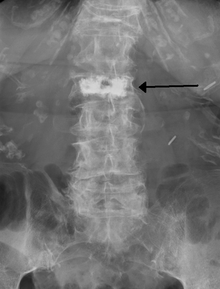

During the procedure, bone cement is injected with a biopsy needle into the collapsed or fractured vertebra. The needle is placed with fluoroscopic x-ray guidance. The cement (most commonly PMMA, although more modern cements are used as well) quickly hardens and forms a support structure within the vertebra that provide stabilization and strength. The needle makes a small puncture in the patient's skin that is easily covered with a small bandage after the procedure.[19]